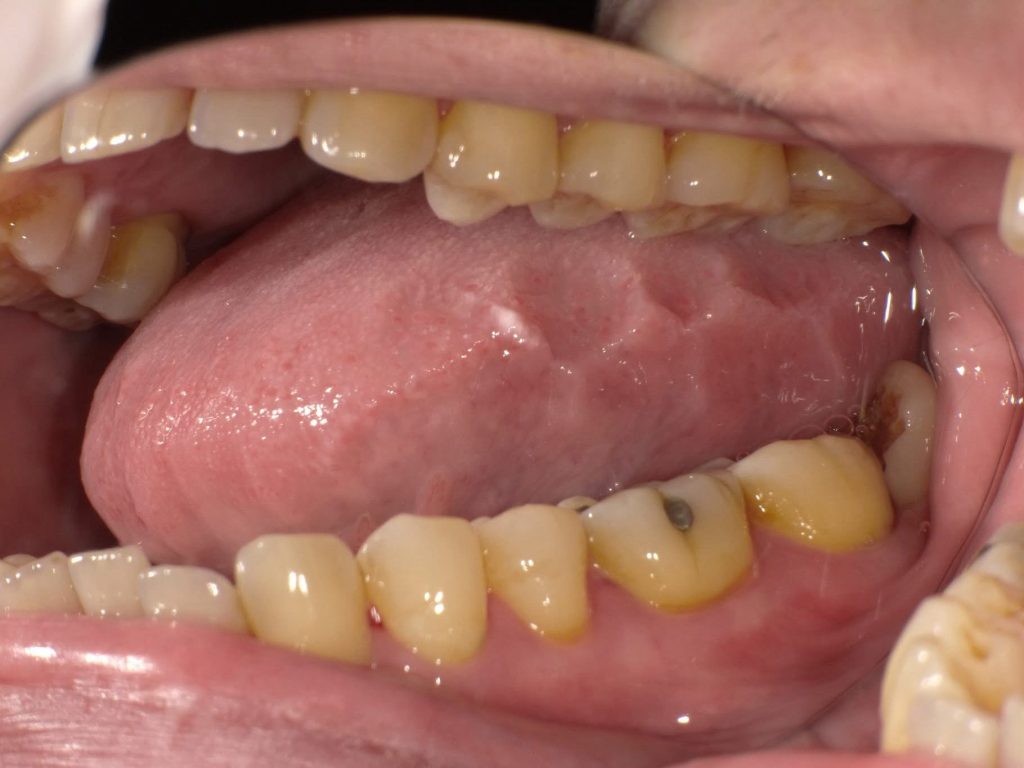

舌の横が凸凹している…それは、ゴザや畳の上で長く正座して脛に跡がつくのと同じ現象です。

そんな「無意識の噛みしめ」が、舌のギザギザサインとして表れているのです。

舌のギザギザは「あなたの無意識が疲れている」サイン。